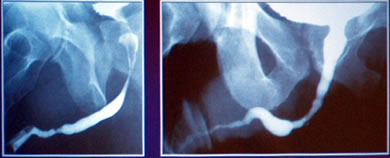

Ишемия